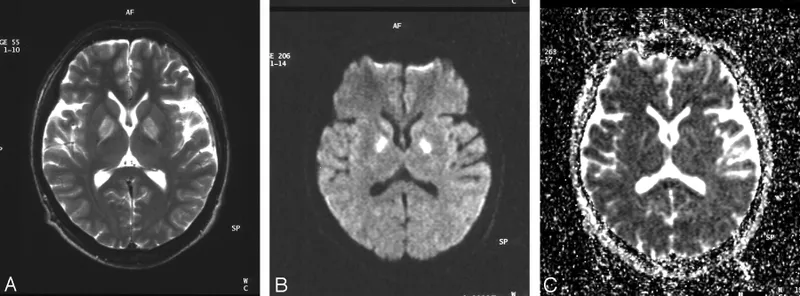

- Bilateral symmetrical necrosis of globus pallidus and hippocampus.